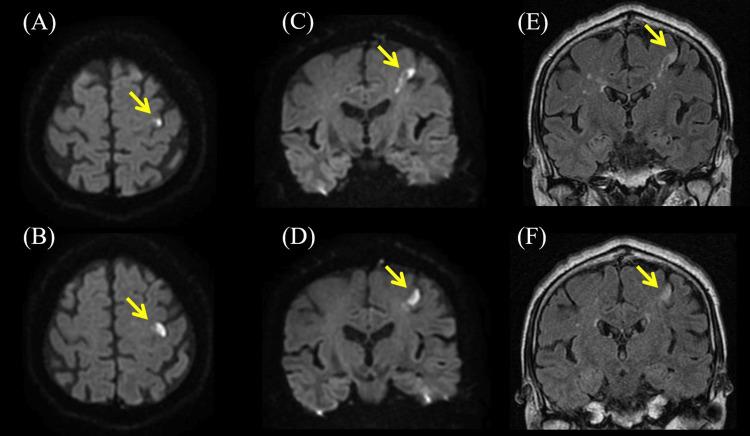

There are various causes of unilateral finger palsy. Its potential etiologies include peripheral neuropathy, carpal tunnel syndrome, and nerve root disorder due to myelopathy. In addition to them, similar paralysis has been reported in localized lesions of the cerebrum, classically referred to as pseudoperipheral palsy. In this report, we describe a case of an 80-year-old man who developed sudden clumsiness of the right fingers. Neurological examination showed muscle weakness mainly in the 1st and 2nd fingers (Medical Research Council grade 1-4) and normal reflexes in the extremities. The affected muscles were innervated by the median nerve, ulnar nerve, and radial nerve, and their nerve root levels ranged from C6 to T1. All the Phalen's, Tinel's, and flick signs were negative. Diffusion-weighted brain magnetic resonance imaging showed hyperintensity limited in the precentral knob on the left precentral gyrus. The etiology was diagnosed as cardiogenic embolism due to atrial fibrillation. In this report, we provide key findings for diagnosing pure motor isolated finger palsy by cerebral infarction through neurological examination.

单侧手指麻痹有多种病因。其潜在病因包括周围神经病变、腕管综合征以及脊髓病导致的神经根疾病。除此之外,在大脑局部病变中也有类似麻痹的报道,经典地称为假性周围性麻痹。在本报告中,我们描述了一例80岁男性突发右手手指笨拙的病例。神经学检查显示主要是示指和拇指肌肉无力(医学研究委员会分级1 - 4级),四肢反射正常。受累肌肉由正中神经、尺神经和桡神经支配,其神经根水平从C6到T1。所有的Phalen试验、Tinel征和弹拨征均为阴性。扩散加权脑磁共振成像显示高信号局限于左侧中央前回中央前结节。病因诊断为心房颤动所致的心源性栓塞。在本报告中,我们通过神经学检查提供了诊断脑梗死所致纯运动性孤立手指麻痹的关键发现。